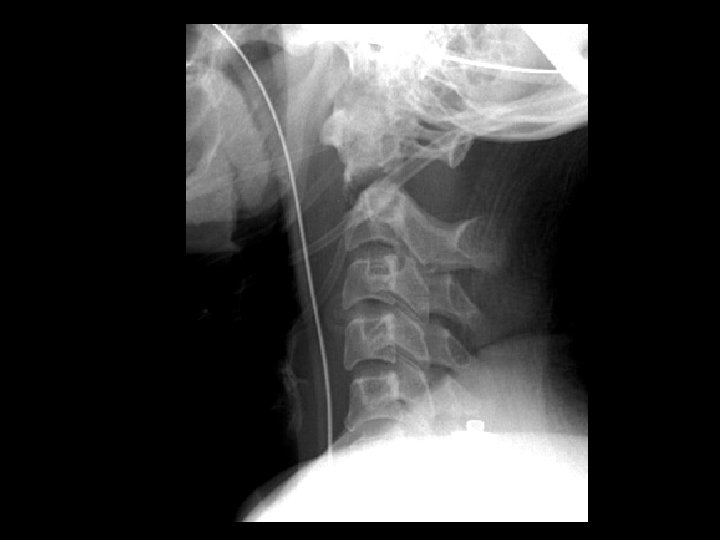

Unilateral jumped facet • Findings: – anterolisthesis of C 5 on C 6, less than 50% – discordant rotation (C 25 bodies appear smaller than C 6 -7) – C 5 inferior facet perched on C 6 superior facet – mechanism: flexion and rotation – STABLE